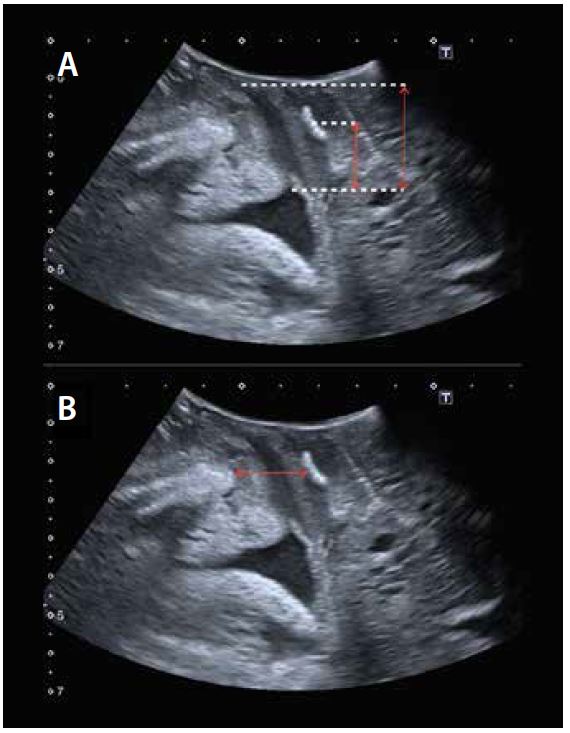

Оцінка середнього відділу

Під час ультразвукової оцінки середнього відділу дуже важливо оцінити рухливість матки, щоб визначити різницю між опущенням матки та подовженням шийки матки без опущення матки. Параметром, який найкраще дозволяє діагностувати опущення матки, є різниця між станом спокою та маневром Вальсальви між лобково-матковим дном (червона лінія на мал. 7) понад 15 мм.

Малюнок 7. Діагностика опущення матки з різницею між положенням спокою (A) і положенням Вальсальви (B), відстань між лобком і матковим дном > 15 мм.